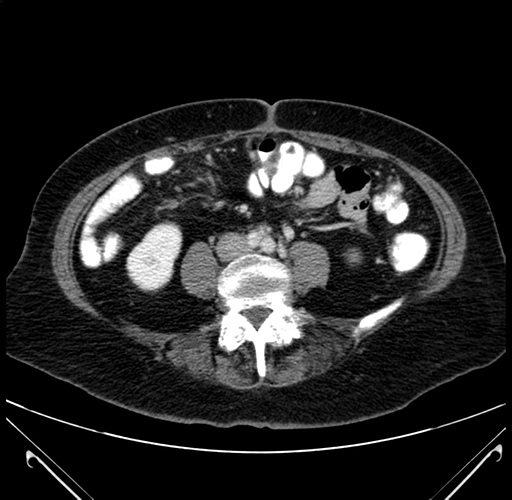

Pre-Chemo: Axial Venous

Axial Venous